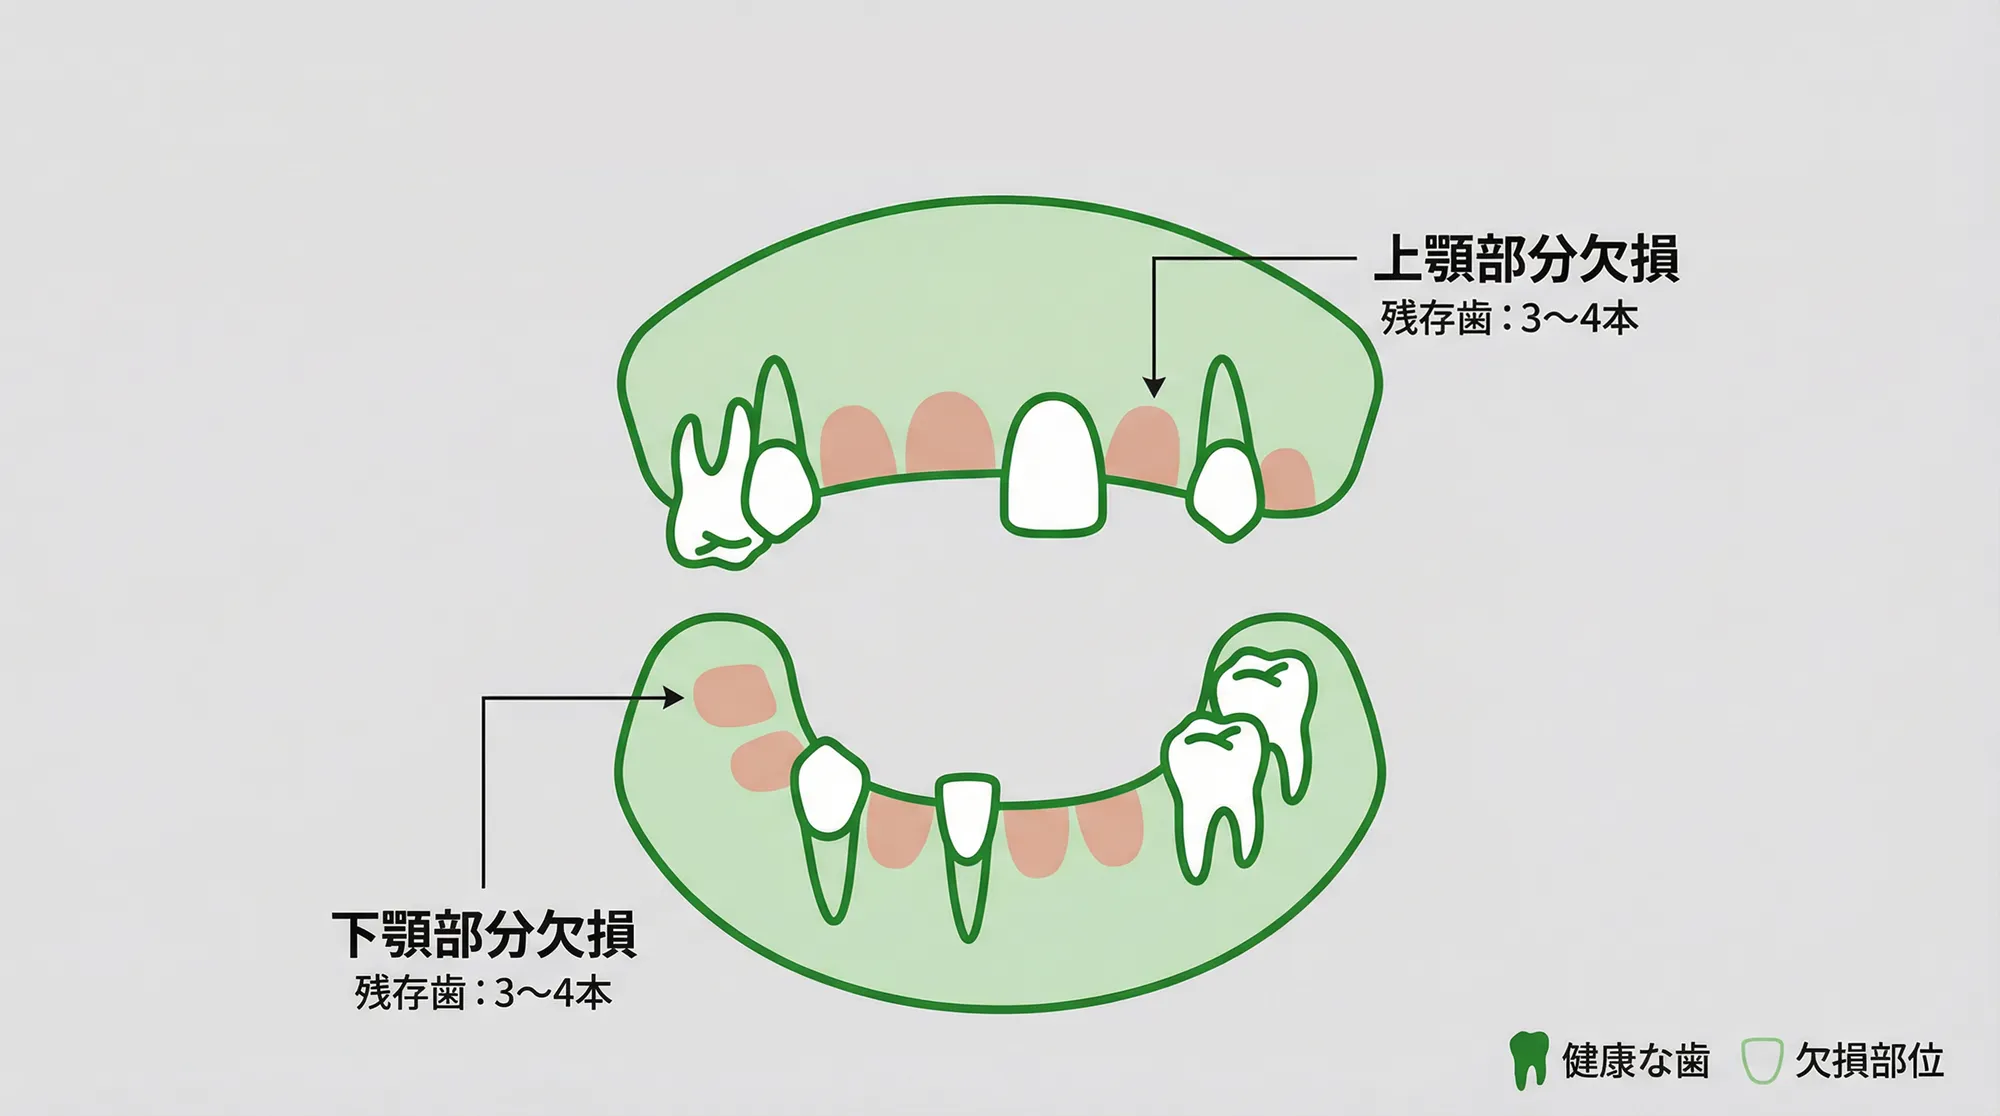

オールオン4・6はこんな方におすすめです

オールオン4・6は以下のような患者様に適しています。

部分入れ歯を使用しているが、残っている自分の歯が少なくよく噛めない

歯がない部分にインプラントを入れると4本以上のインプラントが必要になってしまう

残っている歯が少ない

多くの歯を失い、残っている歯も少ない状態では、部分入れ歯やブリッジでは十分な噛み合わせを得ることが難しくなります。残りの歯に負担がかかり、さらに歯を失ってしまうリスクも高まります。

オールオン4・6なら、少ない本数のインプラントで全体の歯を支えることができるため、残っている歯への負担を軽減しながら、しっかりとした噛み合わせを取り戻すことができます。

Case 3:上顎部分欠損に対するオールオン6

| 治療内容 | 上顎部分欠損に対するオールオン6によるインプラント治療 |

Case 4:上顎部分欠損に対するオールオン6

| 治療内容 | 上顎部分欠損に対するオールオン6によるインプラント治療 |

数本の歯が残っていても治療を受けられますか?

はい、歯が残っていても治療を受けることができます。オールオン4・6治療は、抜歯、インプラント埋入、仮歯装着を1日で行う治療です。残っている歯の状態を精密検査で確認し、抜歯が必要な歯は手術当日に抜歯を行います。その後、インプラントを埋入し、仮歯を装着します。